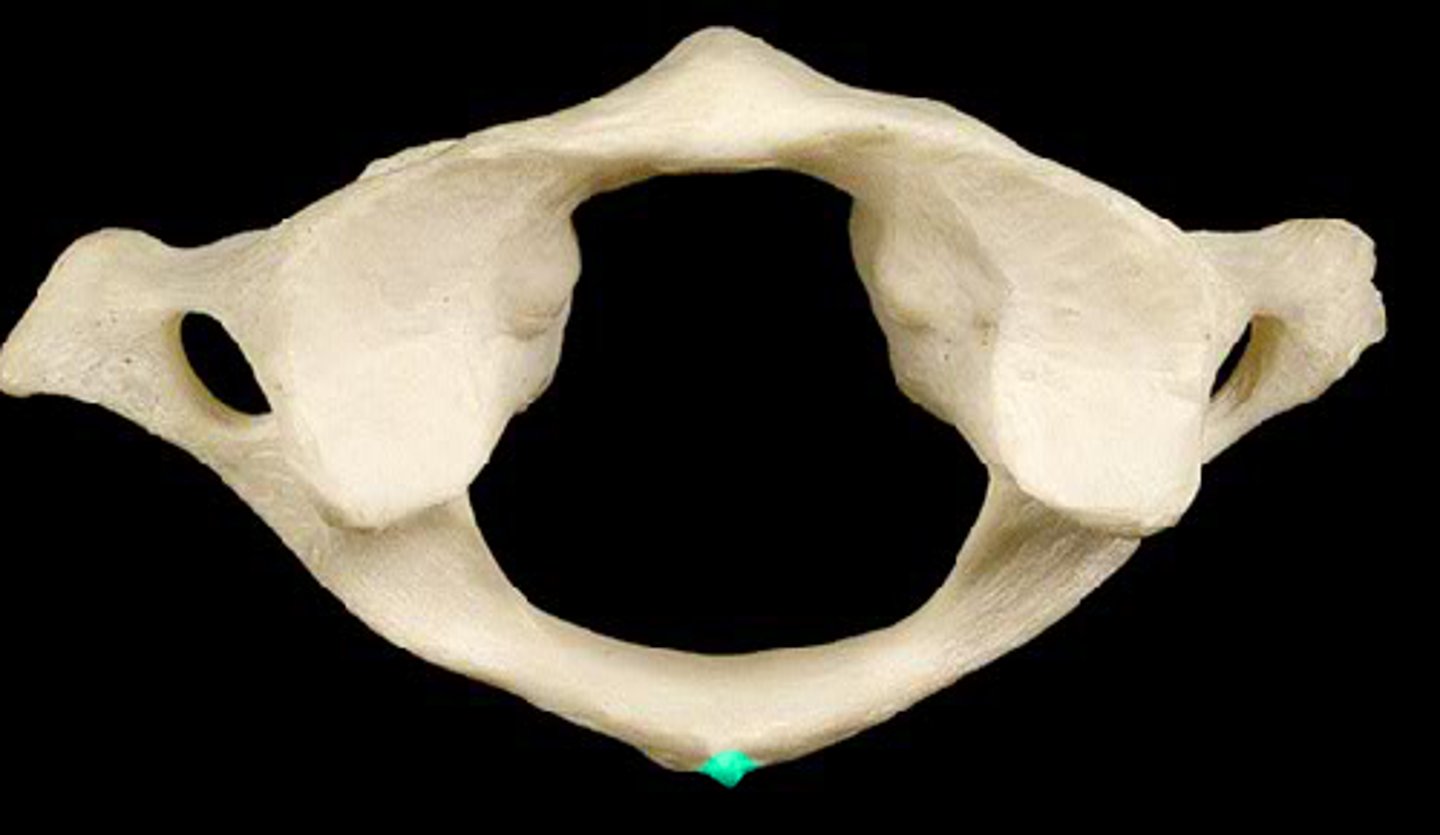

transverse formen (cervical)

vertebral formen

posterior arch

posterior tubercle

atlas C1

what vertebra is considered the atlas

hold head up

what is the purpose of C1

what vertebra is visually a flat bone